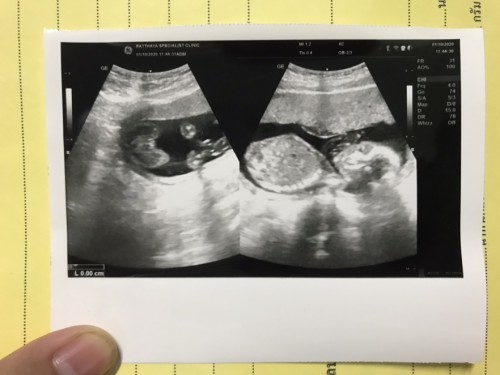

รูปนี้เป็นรูปตอน 34วีค ค่ะ น้องกลับหัวแร้ว แต่พอมาอาทิตย์นี้ 36วีค ไปตรวจตามหมอนัด คุณหมอบอกน้องเอาตูดลงมาแทน แม่ควรทำยังไงดีค่ะ คุณหมอบอกว่าถ้าอาทิตย์หน้า วันที่ 31 มกราคม น้องยังไม่กับหัวต้องผ่าคลอด แต่กำหนดคลอดจริงๆ คือ 16 กุมภาพันธุ์ #ท้องแรกคะ ขอคำแนะนำหน่อยน่ะค่ะ #ขอบคุณสำหรับคำตอบค่ะ